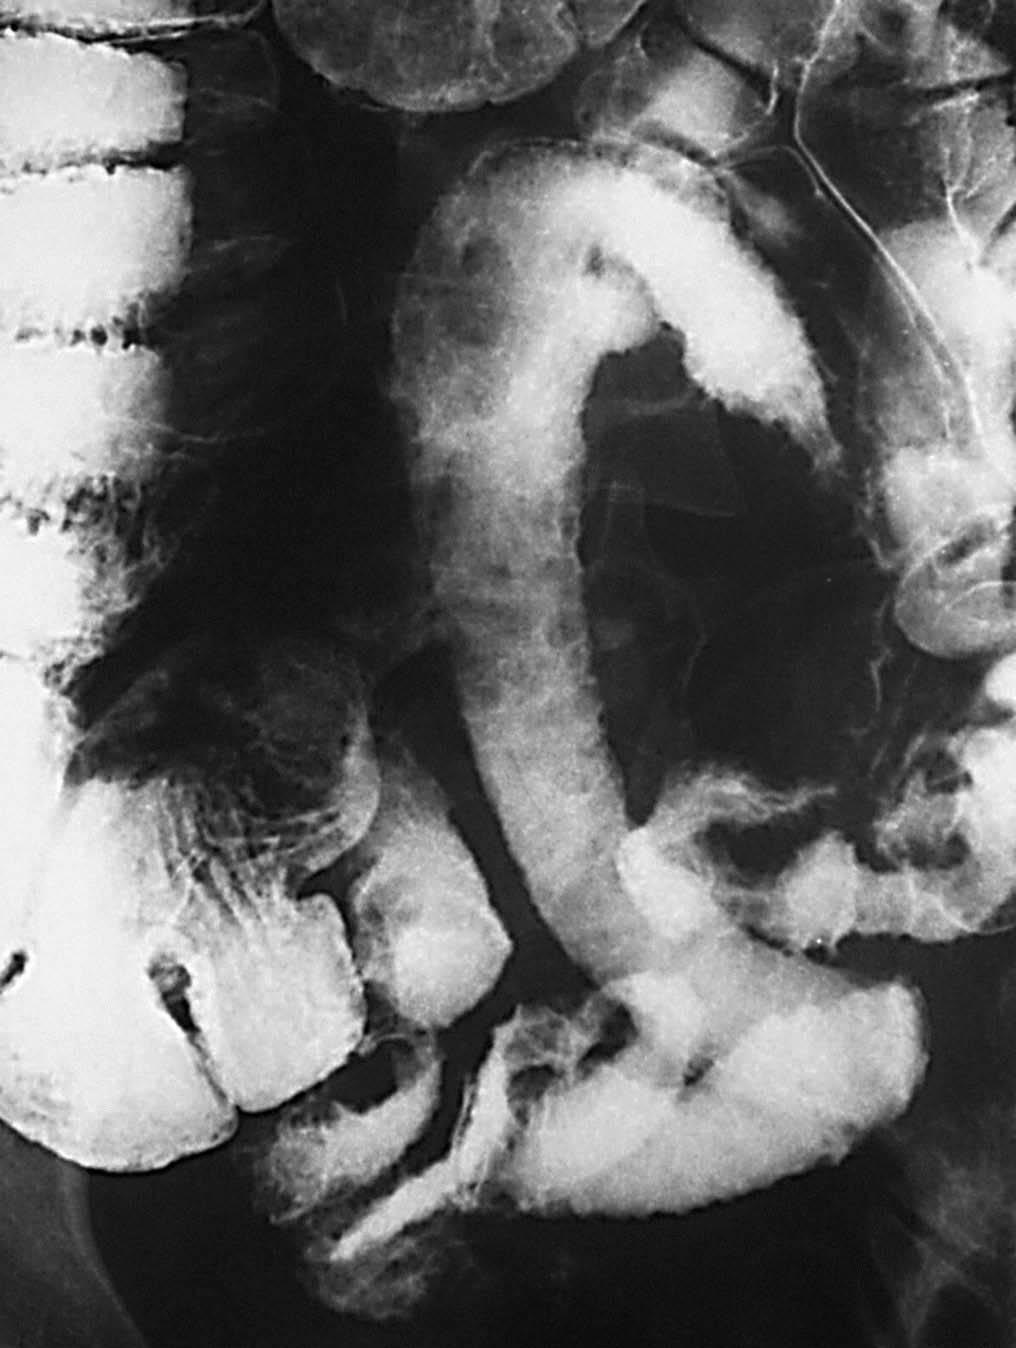

En la etapa inicial los hallazgos propios de la EII en el tránsito baritado son muy sutiles, tal vez discreto grado de espasmo con cierto grado de irritabilidad o alteración de la distensibilidad. De ahí que el estudio baritado tiene que ser realizado con una técnica exquisita, con sumo detalle, con compresión cuidadosa de cada una de las diferentes asas (fig. 3).

Fig. 3.--Enfermedad de Crohn, fase activa inflamatoria. (A) Discreto enderezamiento, rectificación y engrosamiento de pliegues intestinales a nivel de las asas yeyunales. (B) La correlación de tomografía computarizada (TC) muestra la hiperemia y la estratificación tan propias de la situación inflamatoria activa de la pared intestinal.

En la fase activa hay presencia de úlceras superficiales o aftoides (fig. 4). Pueden evolucionar haciéndose ulceraciones fisurantes longitudinales y transversales, dejando entre sí islotes de mucosa normal, constituyendo el concepto de patrón en "empedrado" (fig. 5).

Fig. 5.--Enfermedad de Crohn, fase activa inflamatoria. (A) Ulceraciones longitudinales y transversales que dejan entre sí islotes de mucosa edematosa, constituyendo el patrón en "empedrado" en el estudio baritado. (B) Correlación microscópica: ulceración fisurante rodeada del infiltrado inflamatorio, lesión claramente delimitada y rodeada de mucosa normal.

Al nivel de íleon terminal el espasmo justifica el signo de "la cuerda" (fig. 6). En relación no sólo con el espasmo, sino con una proliferación fibroadiposa del mesenterio aparece el signo del "asa orgullosa" en el estudio con bario, cuyo sustrato fisiopatológico ilustra la TC (fig. 7).

Fig. 6.--Enfermedad de Crohn, fase activa inflamatoria. (A) En el tránsito baritado: signo de "la cuerda" a nivel del íleon terminal. (B) La correlación en tomografía computarizada (TC) muestra engrosamiento mural, hiperemia y estratificación.

Fig. 7.--Enfermedad de Crohn, fase activa inflamatoria. (A) Signo del "asa orgullosa" en el tránsito intestinal. (B) Correlación tomodensitométrica: separación del asa intestinal del resto en relación con proceso inflamatorio de la grasa mesentérica.